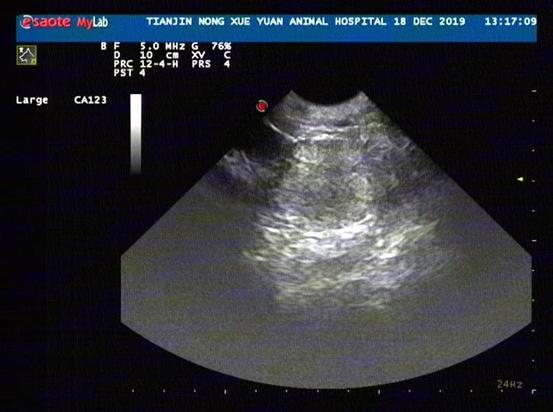

1月后X超声检查结果

1月后复查情况良好,期间并未出现排尿困难及尿血的情况,X光见结石减少,前列腺基本恢复正常大小。B超前列腺大小正常,无囊肿。